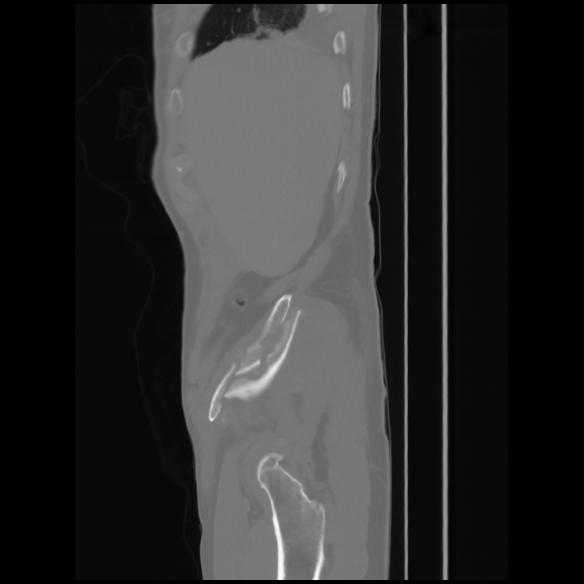

7 CUERPO,CE,Sagittal,3.000,CUERPO,Sagittal,